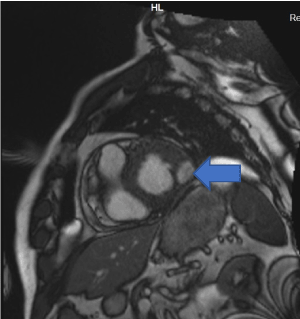

Cardiac MRI showed mildly increased left ventricular (LV) volume indices (End Diastolic Volume - 148mls, End Diastolic Volume Indexed - 71mls, and End Systolic Volume - 75mls, End Systolic Volume Indexed - 31mls) and mildly impaired LV systolic function with LV ejection fraction 48%, normal right ventricular systolic function, and a well circumscribed lesion in the basal lateral wall (Figures 3 and 4). The lesion was hypointense in TruFISP, hyperintense in T1 and T2 weighted images which suggested the lesion did not contain water or fat.  The lesion showed strong homogenous high intake enhancement with gadolinium contrast both in the early and late phase suggesting it was highly vascular. The perfusion study demonstrated a fixed perfusion defect around the lesion. In the gadolinium study, there was no evidence of LV or RV thrombus in the early phase while in the late phase, there was a patch of full thickness late gadolinium enhancement (LGE) around the lesion (Figure 5).

Figure 3. Well circumscribed hypointense lesion in basal lateral wall of left ventricle seen in short axis SSFP cine (Blue arrow).